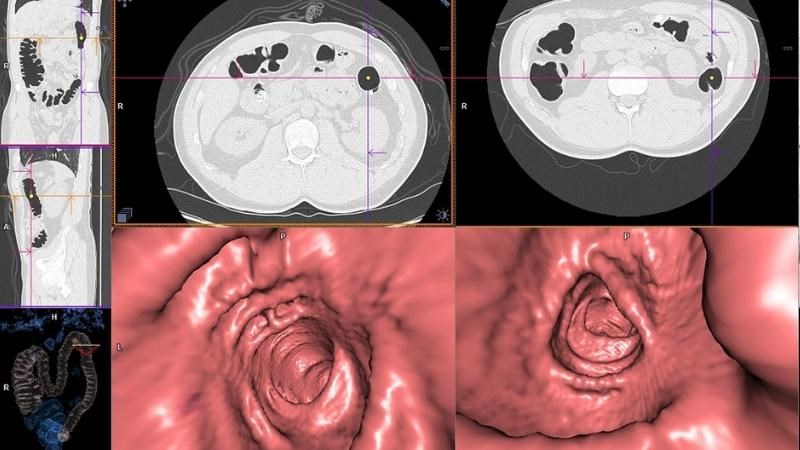

Chụp cắt lớp vi tính đại trực tràng (nội soi đại tràng ảo)

Chụp cắt lớp vi tính đại trực tràng không chỉ cho phép đánh giá được sự xuất hiện của khối u hay các tổ chức bất thường ở đại trực tràng mà còn giúp bác sĩ đánh giá tình trạng xâm lấn của khối u sang các mô, cơ quan xung quanh.

Mặt khác, xét nghiệm này giúp kiểm tra tình trạng hạch ổ bụng và các tạng khác nếu nghi ngờ có di căn ở giai đoạn muộn của ung thư đại tràng.

Chụp cắt lớp vi tính đại trực tràng kết hợp nội soi đại tràng ảo là một xét nghiệm tiên tiến